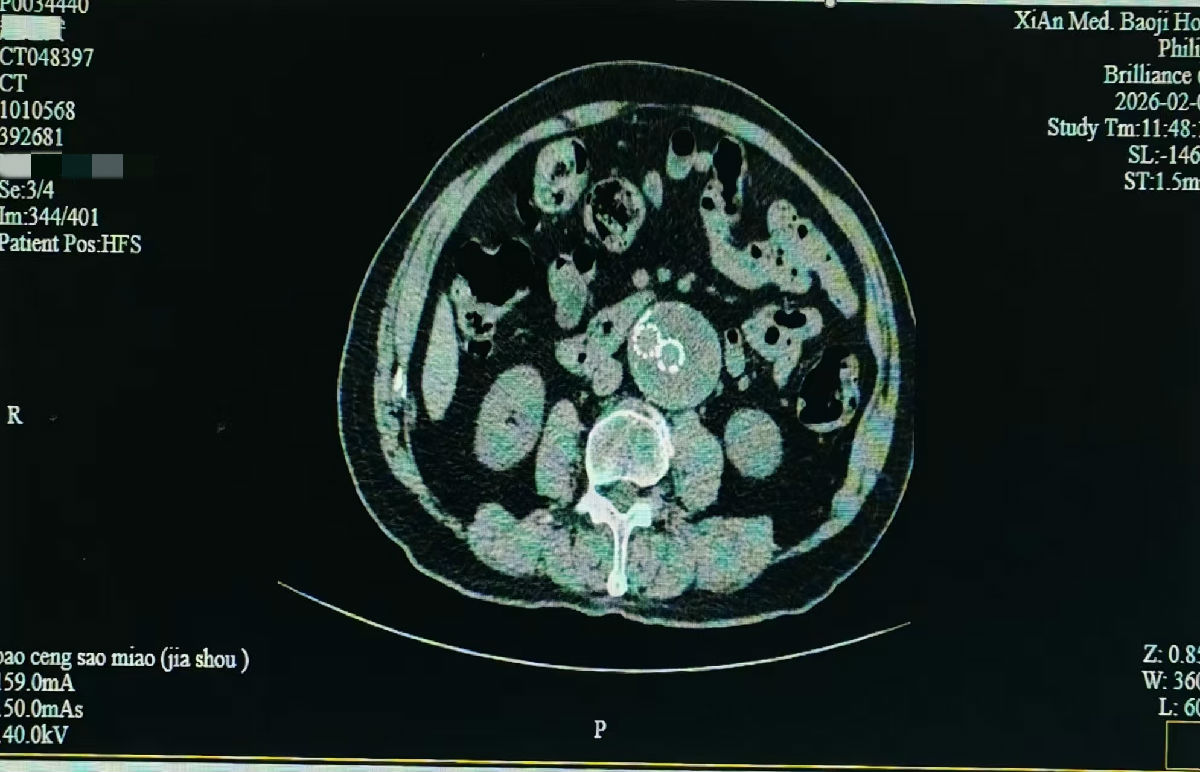

该患者因不明原因身体不适来我院就诊,超声医学科成为探查病情的“第一关”。腹主动脉夹层动脉瘤起病隐匿、进展凶险,诊断难度极高。科室团队凭借扎实的技术与丰富的经验,在细致检查中敏锐捕捉到可疑征象。为谨慎起见,医院迅速启动多学科会诊(MDT),超声医学科与医学影像科专家共同研判、交叉验证,最终明确诊断为腹主动脉夹层动脉瘤,为后续治疗争取了宝贵的“黄金时间”。

“此类疾病的救治,关键在于早发现、准判断。”超声医学科主任赵君智主任医师指出。超声以其无创、便捷、实时成像的优势,成为该病筛查与初诊的重要工具。此次精准诊断不仅为治疗提供了关键依据,也为后续向华西医院转诊搭建了扎实的沟通基础。鉴于病情复杂危重,我院在完成全面评估与稳定病情后,积极协助患者转至国内顶尖的四川大学华西医院进一步治疗。

华西医院心脏大血管外科团队针对患者病情特点,精心设计了“人字形支架植入术”,手术中,将支架从腹主动脉脐部水平植入,延伸至双侧髂总动脉,实现对病变血管的全程覆盖与有效支撑,成功封闭夹层破口,高难度完成手术,为患者解除生命威胁。